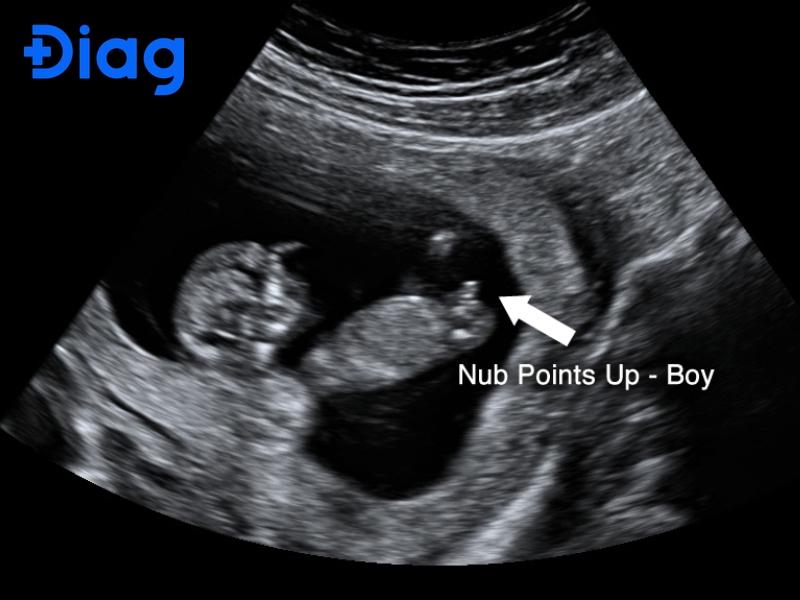

Hình ảnh siêu âm bé trai như thế nào?

Khác với bé gái, hình ảnh siêu âm bé trai thường dựa trên việc quan sát dương vật và bìu. Trên hình ảnh siêu âm, bác sĩ thường tìm kiếm ‘dấu hiệu con rùa’ (turtle sign) đặc trưng ở tam cá nguyệt thứ hai. Trên mặt cắt ngang siêu âm, cấu trúc này bao gồm một phần nhô ra (dương vật) kèm theo hai khối tròn nhỏ (bìu) nằm giữa hai đùi của thai nhi. Đây là dấu hiệu sinh dục ngoài đặc trưng của bé trai khi đã phát triển đầy đủ.

Tuy nhiên, ở một số thời điểm, dây rốn hoặc bàn tay thai nhi có thể nằm đúng vị trí này, khiến hình ảnh dễ bị nhầm lẫn. Không ít trường hợp bố mẹ tự xem hình siêu âm bé trai trên mạng rồi so sánh với kết quả của mình và kết luận vội vàng.

Do đó, siêu âm bé trai cần được thực hiện đúng thời điểm, với kỹ thuật siêu âm phù hợp và máy móc đủ độ phân giải, để hạn chế tối đa sai sót.